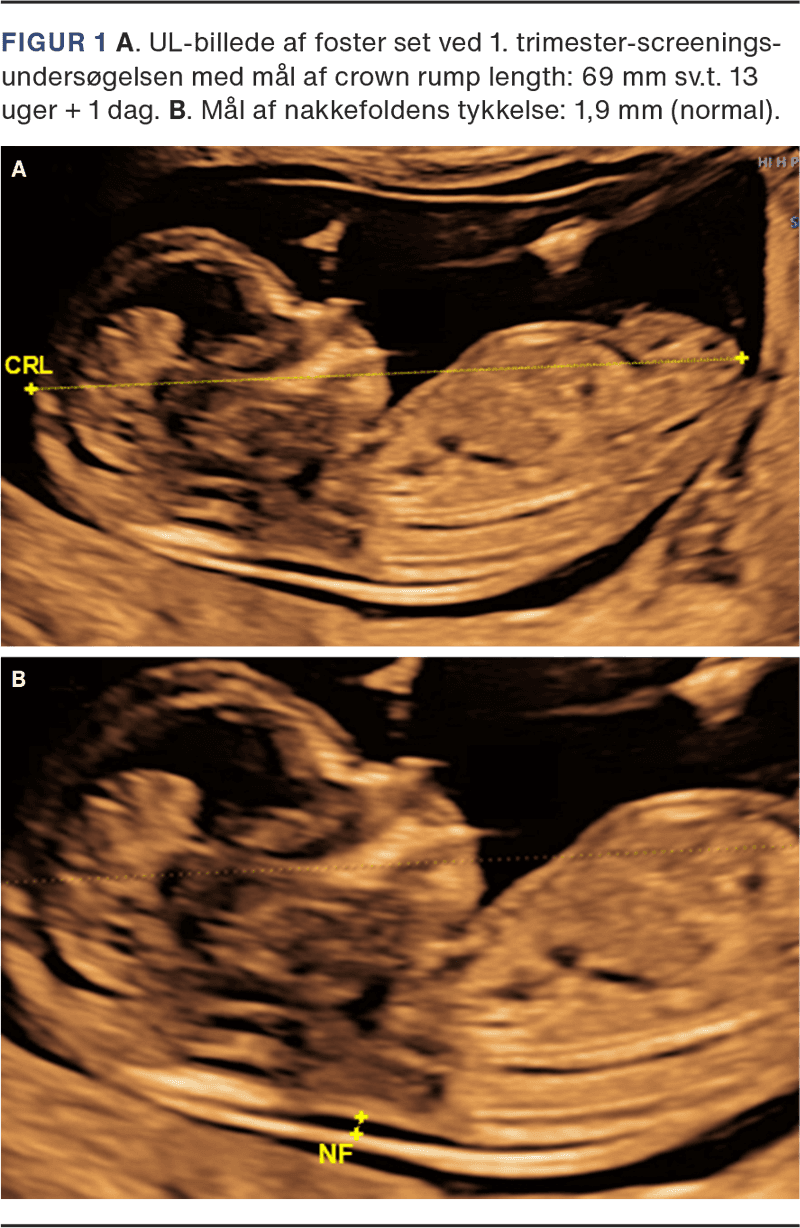

1. trimester-screeningsundersøgelsen er et tilbud til alle gravide, som den gravide informeres om hos egen læge i forbindelse med første svangreundersøgelse. Undersøgelsen foretages ved GA 11-14 uger af en sonograf, der er certificeret i nakkefold (NF)-skanning. Ved skanningen undersøges for fosterhjerteaktivitet, antal fostre samt for choriositet ved flerfoldsgraviditet. GA bestemmes ved måling af crown rump length (CRL) (Figur 1 A). Herudover måles NF-tykkelse (Figur 1 B), hvis den gravide ønsker sandsynlighedsvurdering for trisomi 21, trisomi 18 og trisomi 13. Fosteret undersøges desuden for større misdannelser, herunder større CNS-misdannelser (f.eks. anencefali), svære hjertemisdannelser, bugvægsdefekter og større skeletmisdannelser (f.eks. manglende ekstremiteter). Sandsynlighedsvurderingen beregnes ud fra den gravides alder, NF-tykkelse og biokemiske markører målt ved en blodprøve. Blodprøven (doubletesten) tages ved egen læge eller på hospital ved GA 8-14 uger. I blodprøven analyseres to proteiner, der begge produceres i placenta: pregnancy-associated-plasma-protein A (PAPP-A) og frit beta-humant choriongonadotropin (fβ-hCG). Den målte koncentration af begge markører omregnes til multiples of the median (MoM)-værdier, da de varierer betydeligt med GA, ligesom de justeres for diverse maternelle karakteristika, der vides at påvirke koncentrationen – bl.a. paritet, vægt, rygning, etnicitet og konceptionsmåde. Alle data samles i det føtalmedicinske softwareprogram Astraia, der udregner sandsynligheden for trisomi 21, 18 og 13. Hvis den gravide har en sandsynlighed for trisomi 21 på ≥ 1:300 og/eller trisomi 18 eller 13 på ≥ 1:150, tilbydes yderligere undersøgelse. Ligeledes tilbydes yderligere undersøgelse ved tilstedeværelse af et af følgende enkeltkriterier for atypiske kromosomfejl: alder ≥ 45 år, NF ≥ 3,5 mm, PAPP-A eller fβ-hCG ≤ 0,2 MoM, fβ-hCG ≥ 5 MoM, eller hvis der er påvist en misdannelse hos fosteret.